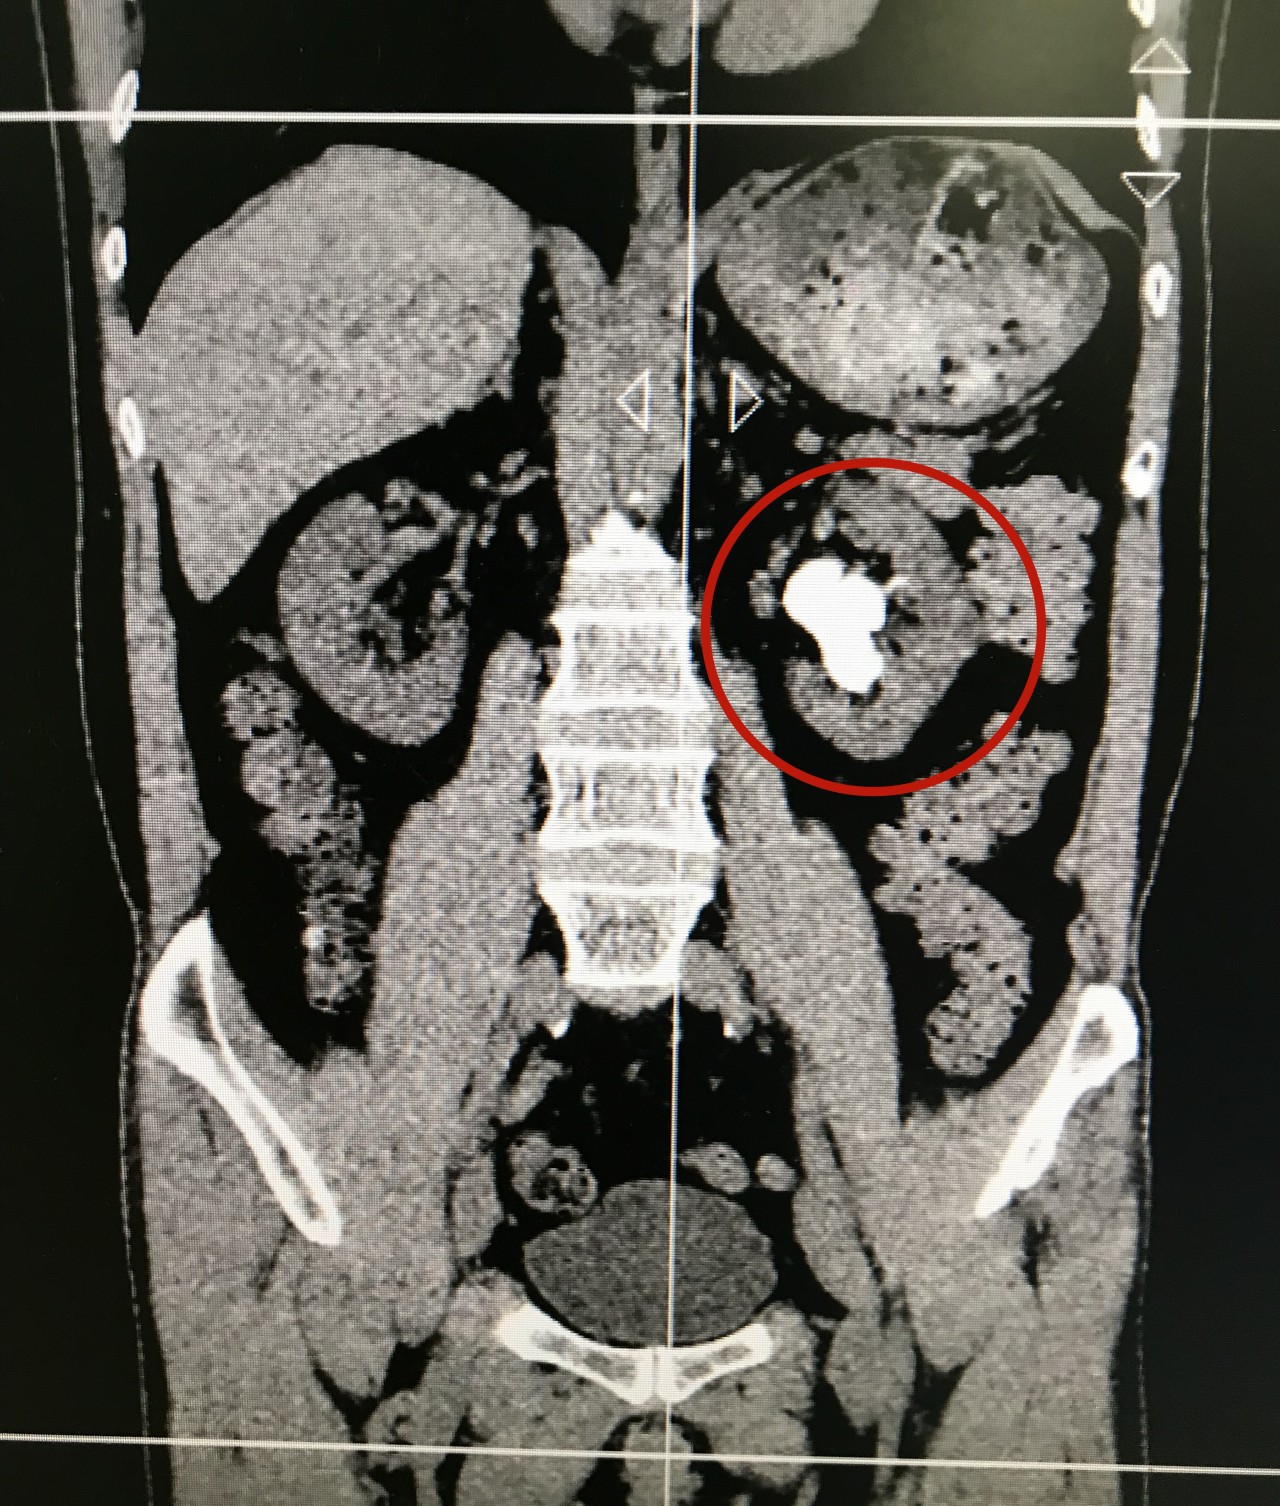

今年50多岁的林先生因查体发现肾结石来到济南市一院泌尿外科就诊,泌尿外科专家们看到林先生的CT后发现,林先生的肾里竟然有一颗直径超过4cm的巨大肾结石。

(林先生的CT:左肾结石)